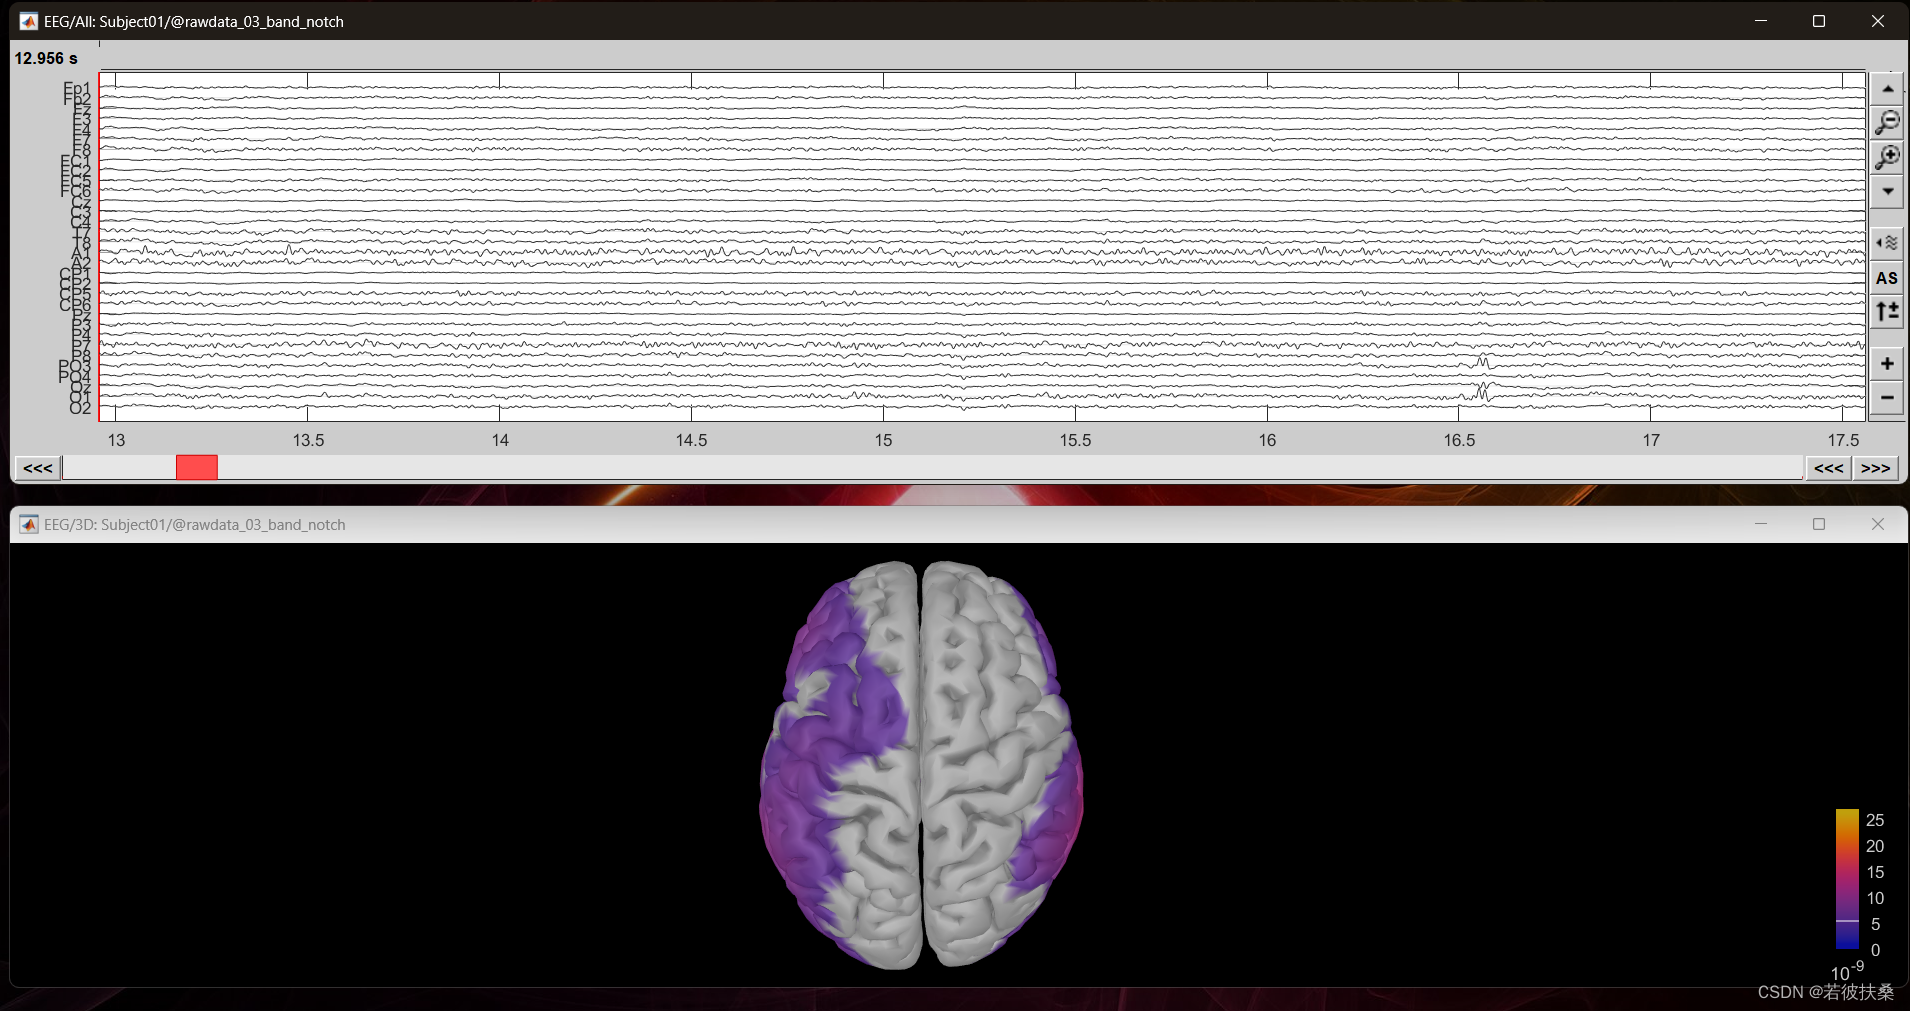

源模型是显示某一个时间点或(某段时间的平均值)的神经活动,拖动曲线下方的红色控件,即可查看不同时间点的时间活动情况。

至此,我们已经完成EEG的源定位,并且获得了一张皮层脑电图,后续作者将会具体讲述如何进行手动ICA去伪迹、以及如何进行源分析。